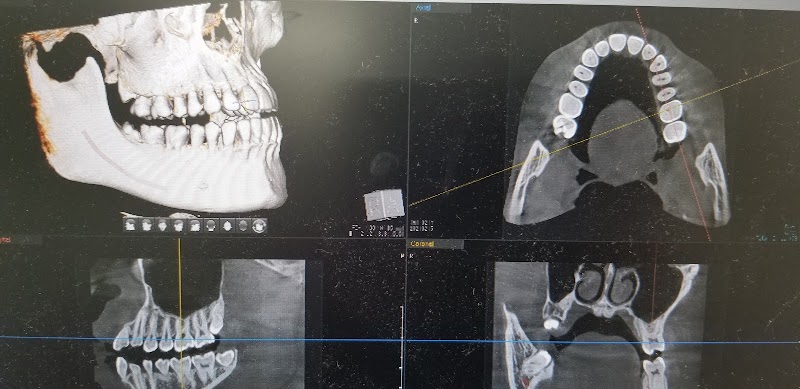

医院長先生が丁寧で、とにかく安心して治療してもらえます。説明も、画像を見せてくれて、分かりやすいと思います。